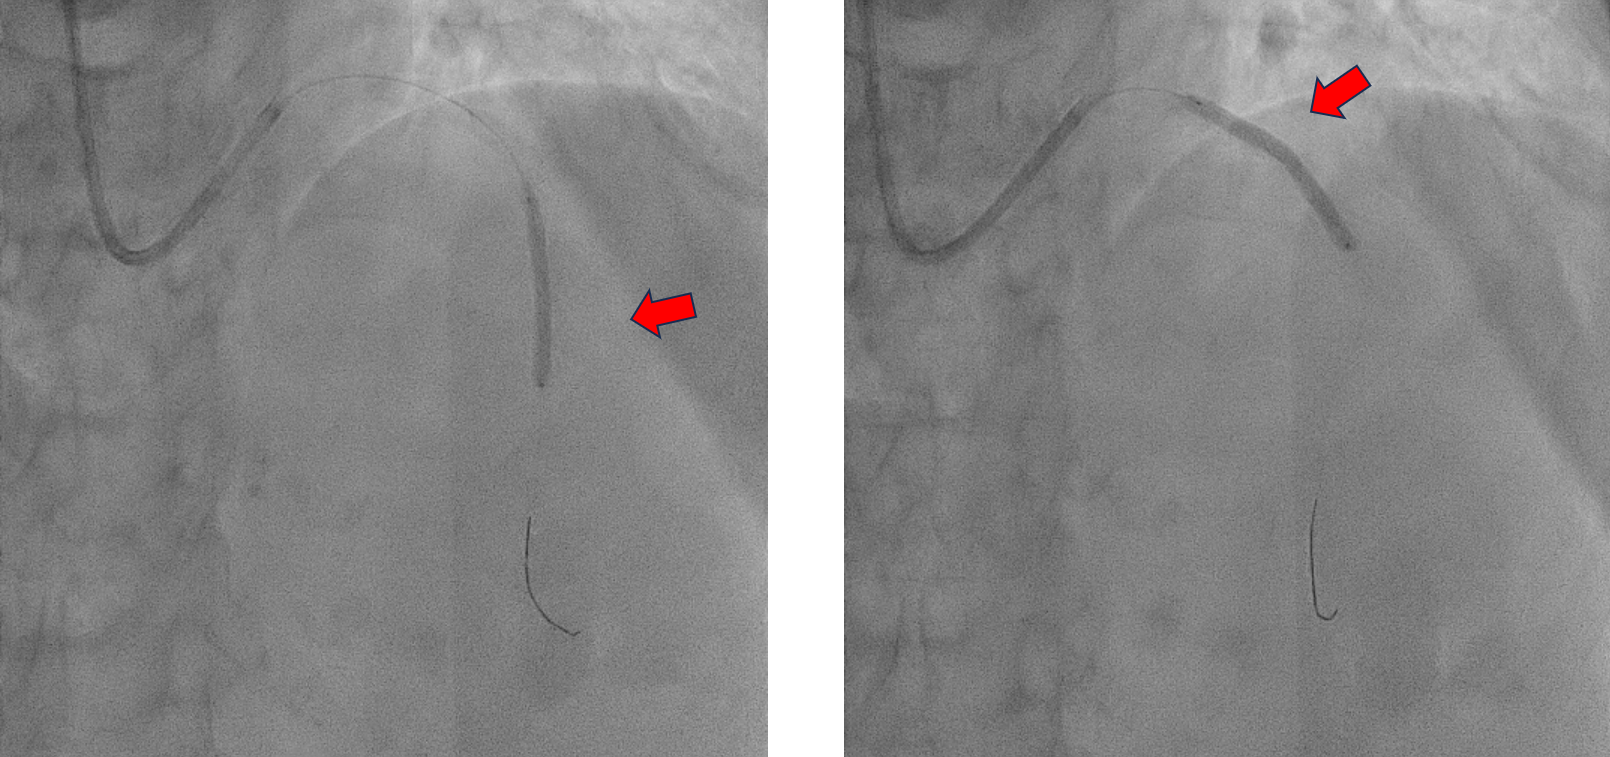

The procedure was performed using a 7 Fr right radial approach. A total of 6000 units of intracoronary heparin and 300 mg of oral clopidogrel were administered. The left coronary system was engaged with a 7 Fr extra-backup (EBU) 3.5 mm guiding catheter, and the lesion was successfully crossed with a Run-through floppy wire extending to the distal LAD. Pre-dilation was performed with a 2.0 mm x 15 mm Genoss balloon, inflated to 16 atm. Intravascular ultrasound (IVUS) imaging revealed 360-degree superficial calcium at the tight LAD lesion, a vessel diameter under 3.5 mm, and a calcium score of 2. The mid-LAD measured 3.0 mm and the proximal LAD measured 4.0 mm. Pre-dilation was performed in the mid-LAD using a 3.0 mm x 16 mm Genoss non-compliant (NC) balloon, and in the proximal LAD with a 3.5 mm x 20 mm NC Emerge balloon, both inflated to 16 atm. Post-pre-dilation IVUS imaging showed cracking of the superficial calcium with vessel expansion to 3.0 mm. Subsequently, drug-coated balloon (DCB) angioplasty was performed with a 3.0 mm x 30 mm Magic Touch DCB in the mid-LAD and a 3.5 mm x 35 mm Magic Touch DCB in the proximal LAD. Final angiography demonstrated a non-flow-limiting Type A dissection with less than 30% recoil, and the procedure was successfully concluded.